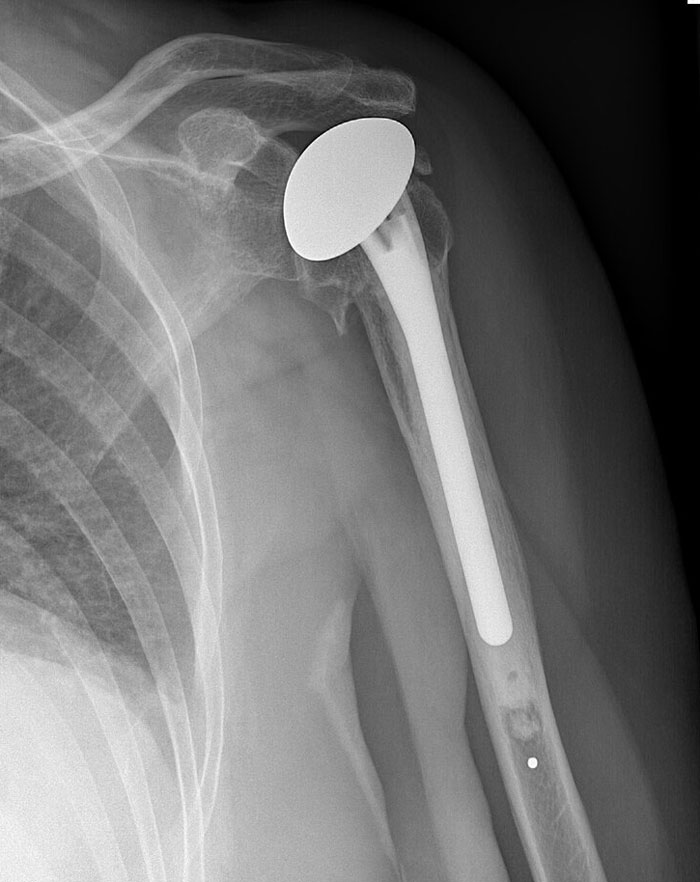

Estábamos trabajando en la zona del hombro y chocamos con algo duro. No era un hueso e hizo un ruido metálico.

Resulta que nuestro cadáver tenía un reemplazo de articulación del hombro y estábamos golpeando la "bola" metálica (¿a falta de un término mejor?).

No parece gran cosa, pero ¡asustó muchísimo a un montón de estudiantes de segundo año!